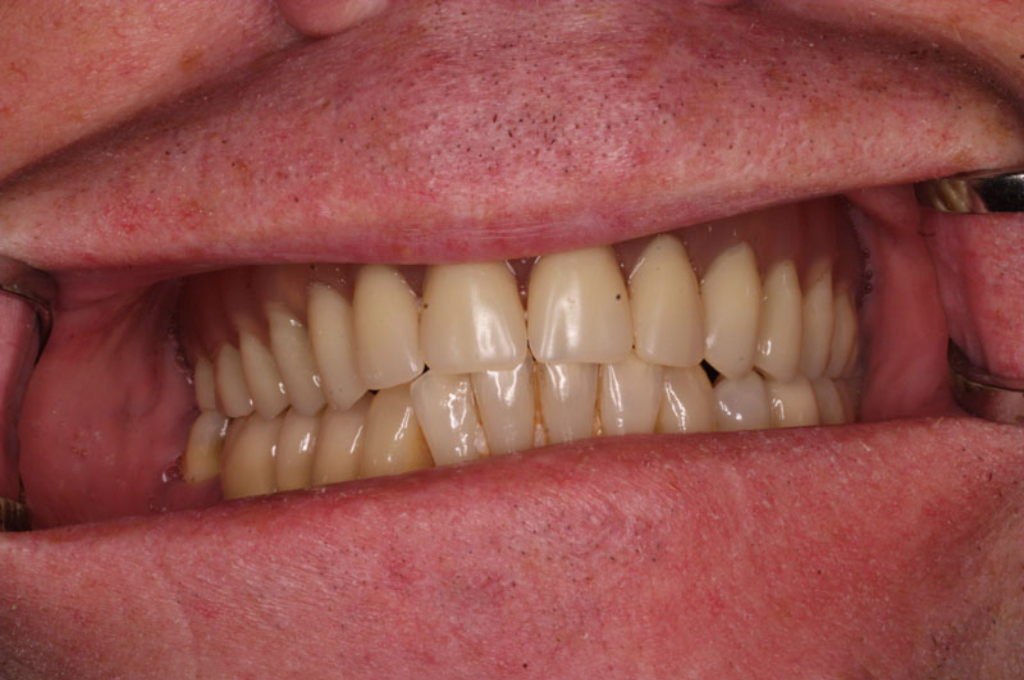

Implantáty jsou osvědčeným a vyzkoušeným řešením, které dnes umožňuje zhotovení estetické a funkční náhrady.

• Dokonalé obnovení funkce a estetiky

• Možnost mluvení, kousání a vnímání chuti jako u vlastních zubů